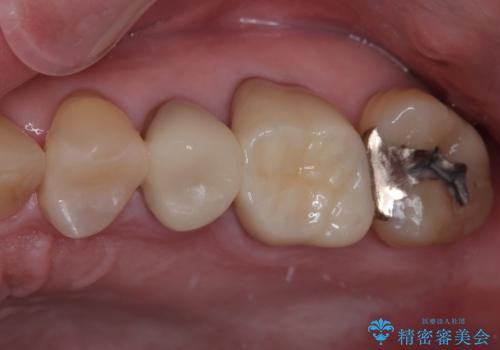

特に異常もなく見た目、噛み合わせともに満足していただけました。

ラバーダム防湿を行い、セラミックの接着をすることで、唾液や血液などの接着阻害因子を排除することができます。